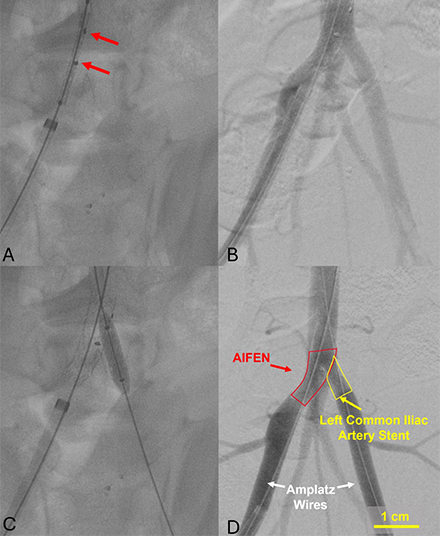

Methods: AIFEN stents were fabricated by cutting 7 mm fenestrations into from 10×55 mm balloon-expandable covered stents, suturing on radiopaque markers, and re-crimping using a 3D-printed crimper (Figure 1). In vivo feasibility was assessed in 3 anesthetized pigs (two non-survival, one 10-week survival). Right femoral access obtained with a 12 Fr sheath enabled AIFEN deployment from aorta to proximal right common iliac. A 7 Fr sheath in the left femoral artery enabled delivery of a 7×15 mm balloon-expandable covered stent into the left common iliac artery and AIFEN fenestration. The survival pig received daily dual antiplatelet therapy and underwent weekly femoral artery duplex ultrasounds for patency assessment.

Results: AIFEN stent deployment was successful in all three pigs, with demonstrated patency through both AIFEN and contralateral iliac artery stents (Figure 2). Explant analysis showed the AIFEN device and left iliac stent remained in situ without retroperitoneal bleeding or injury (Figure 3). In the survival pig, serial femoral ultrasounds confirmed device patency through week 4, with stable arterial peak systolic velocities (right femoral: 84-90 cm/s; left femoral: 81-90 cm/s).